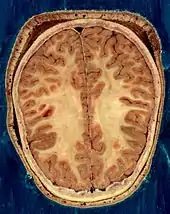

O cérebro, o tronco cerebral, o cerebelo e a medula espinhal são cobertos por três membranas chamadas meninges. As membranas são a dura-máter resistente; a aracnóide e a pia-máter interna, mais delicada. Entre a aracnoide e a pia-máter estão o espaço e as cisternas subaracnoides, que contêm o líquido cefalorraquidiano.[10] A membrana mais externa do córtex cerebral é a membrana basal da pia-máter e é uma parte importante da barreira hematoencefálica.[11] O cérebro vivo é muito macio, tendo uma consistência de gel semelhante ao tofu.[12] As camadas corticais de neurônios constituem grande parte da matéria cinzenta cerebral, enquanto as regiões subcorticais mais profundas dos axônios mielinizados constituem a matéria branca.[6] A substância branca do cérebro representa cerca de metade do volume total do cérebro.[13]

O cérebro é a maior parte do encéfalo e é dividido em hemisférios direito e esquerdo quase simétricos por um sulco profundo, a fissura longitudinal.[14] A assimetria entre os lobos é observada como uma petália.[15] Os hemisférios são conectados por cinco comissuras que abrangem a fissura longitudinal, a maior delas é o corpo caloso.[6] Cada hemisfério é convencionalmente dividido em quatro lobos principais; o lobo frontal, o lobo parietal, o lobo temporal e o lobo occipital, nomeados de acordo com os ossos do crânio que os cobrem.[7] Cada lobo ou lóbulo está associado a uma ou duas funções especializadas, embora haja alguma sobreposição funcional entre elas.[16] A superfície do cérebro é dobrada em cristas (giros) e ranhuras (sulcos), muitos dos quais são nomeados geralmente de acordo com sua posição, como o giro frontal do lobo frontal ou o sulco central, que separa as regiões centrais dos hemisférios. Existem muitas pequenas variações nas dobras secundárias e terciárias.[17]

A parte externa do cérebro é o córtex cerebral, composto de matéria cinzenta organizada em camadas. Tem 2 a 4 milímetros de espessura e é profundamente dobrado para dar uma aparência complicada.[18] Abaixo do córtex está a matéria branca cerebral. A maior parte do córtex cerebral é o neocórtex, que possui seis camadas neuronais. O resto do córtex é de alocórtex, que tem três ou quatro camadas.[19]